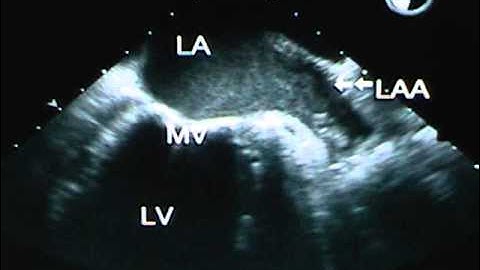

Scanning the Left Atrial Appendage with TEE